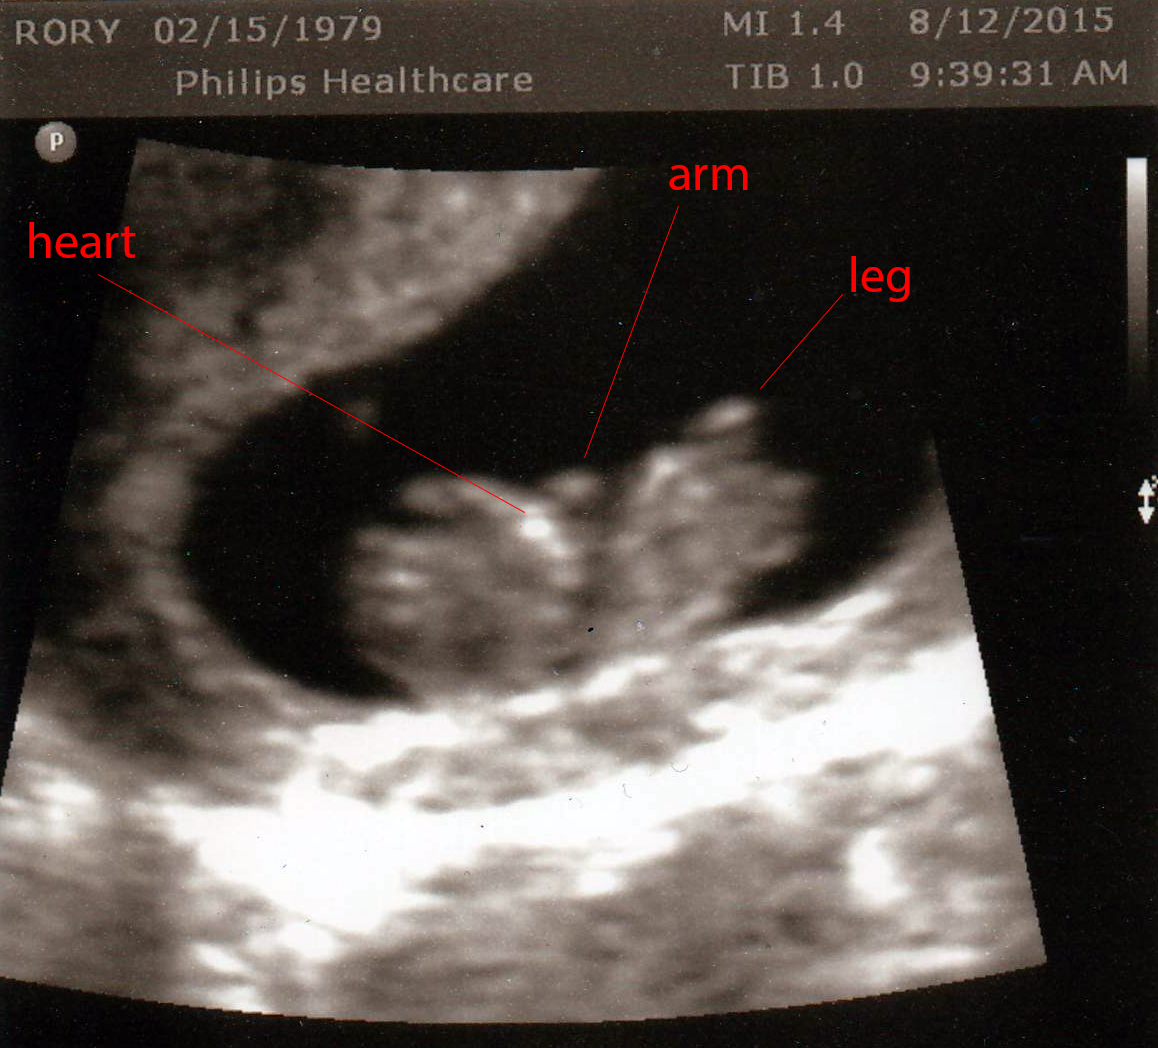

The ultrasound was amaaaaazing. It took about 15 minutes and was sooooo much better than my first ultrasound. The technician would press my belly hard with the ultrasound and you’d see the baby put it’s hands up like “Stop!” And I got to see all sorts of different angles – at one point it was an overhead view and I could actually see the outline of the brain. THE BRAIN! WTH! It was just so crazy. I posted a snippet to my instagram, if you care to watch (link is in the right panel).

No news on the gender front. I had hoped she would be able to see something, but she was quite emphatic that 13 weeks they don’t even attempt to determine the sex, and she barely even looked between the legs (although there were several between the legs shots and I didn’t see anything). However, she did say “he” and “him” a few times when referring to the baby, which I didn’t even notice until I watched the video later that day. Hopefully she was just speaking generically!